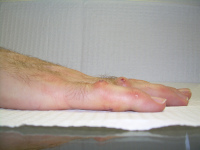

Clinical Example: Dupuytren Distal Interphalangeal Joint Needle Fasciotomy

Dupuytren contracture usually involves the metacarpophalangeal and proximal interphalangeal joints, but occasionally affects the distal interphalangeal joints. This is usually accompanied by proximal interphalangeal joint involvement. This is almost always a lateral rather than a central cord, and may present as a spiral cord, the neurovascular bundle superficial just proximal to the distal interphalangeal joint.

The functional impact of this is that it contributes to the fingertip catching on things like a hook. Isolated interphalangeal joint contractures in the context of hyperextensible metacarpophalangeal joints allow patients to defer evaluation until the contracture is severe.

The most common method of treating this is with fasciectomy, but needle fasciotomy may be effective. Collagenase has been used for this, but is an off-label application.

As with needle release or collagenase treatment of the proximal interphalangeal joint, recurrence is expected: these minimal procedures should be considered a temporizing step with expectations of partial improvement.

The following are examples of percutaneous needle fasciotomy for a variety of contractures involving the distal interphalangeal joint. Portals proximal and/or distal to the distal interphalangeal joint flexion creases are used, some bilaterally.

These are presented to illustrate the diversity of even this subset of Dupuytren disease. None had prior treatment.